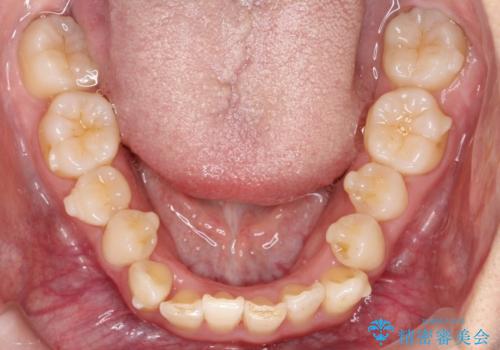

- 患者様は、全体的な歯列のガタガタとディープバイト(深い噛み合わせ)を主訴として来院されました。診断の結果、ディープバイトを改善するためには、歯列全体の拡大が必要であると判断しました。治療には、透明なマウスピース型矯正装置「インビザライン」を使用し、歯を適切に拡大しながら歯並びを整える計画を立てました。治療期間はおおよそ2年を見込んで進め、最終的に見た目にも大きく変化をもたらすことを目指しました。

ディープバイトの治療には、奥歯の高さや前歯の位置に対する繊細な調整が必要です。本症例では、インビザラインによる歯列拡大を行うことで、噛み合わせを改善し、歯並び全体を整えました。治療過程では、歯間のスペースを確保するため、IPR(インタープロキシマルリダクション)を適宜行い、無理なく歯列の調整を行いました。治療後は、歯並びが大きく改善され、患者様の見た目にも大きな変化が現れました。インビザラインは透明で目立たず、治療中の見た目を気にされる患者様にも配慮した治療法です。